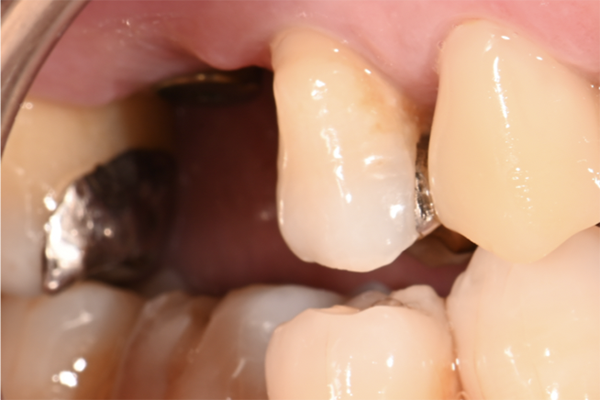

| 主訴 | 奥歯で噛めない、顎が痛い |

|---|---|

| 治療内容 | 奥歯のインプラント治療、前歯・奥歯の被せ物治療 |

| 治療期間 | 6ヶ月 |

| 治療費 | 350万円 |

| 治療リスク | 被せ物をつけた初期の段階で歯がしみることがある(時間とともに改善する) インプラント治療後に3日程度痛みと腫れを伴うことがある |